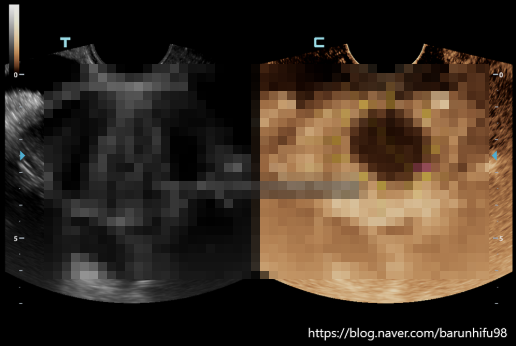

자궁근종 4cm? 더 커지기 전에 <필독>

자궁근종하이푸 1세대 의료진 단독 시술로만 하이푸 2,300례 이상 울트라베라 최다 시술병원 선정 비비브 2...